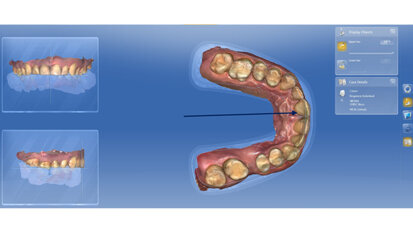

Rehabilitace Straumann